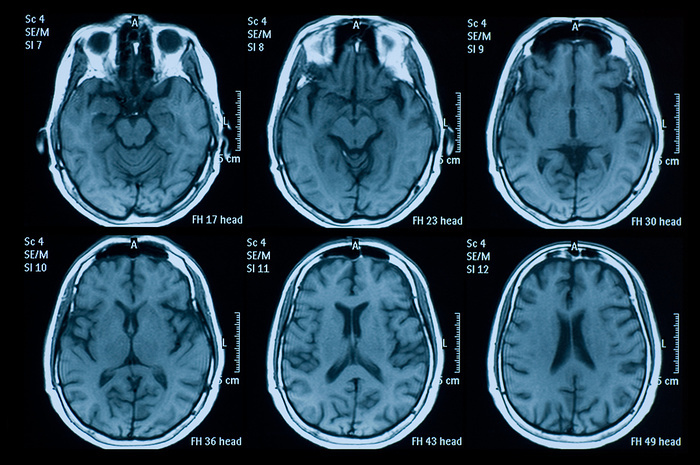

5. DICOM

特点:医学影像专用格式,一般人碰不到

后缀:.dcm

DICOM平时很少见到,这是因为它是医学影像专用的一种格式。比方说CT、核磁、超声等设备,它们得到的信息往往是围绕人体某一部位制作的一个接一个的断面,因此图像也都是多层图像,这时就需要将图片保存为DICOM格式。一般来说,DICOM的使用与生成都是有专用软件的,就算日常显示都不会用到PS,这里的PS只不过是做了一下简单兼容而已。